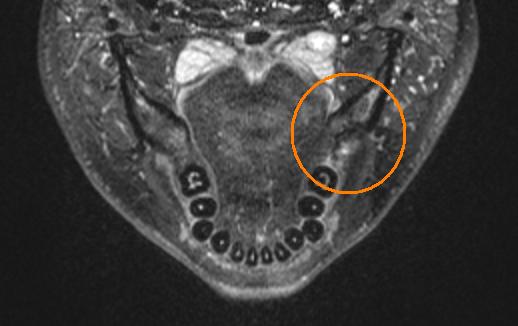

Failure

The previous operation only brought me temporary relief at best. By the time 6 months had come around I seemed to be deteriorating fast. I had developed a really severe chest pain, that extended from my neck half the way down my chest. I had started to lose feeling and taste on the left side of my tongue. My vision was being effected, it was getting really ridiculous. I knew the problem was still there, but x-ray, and cavitat had given me the all clear, and I already had one repeat surgery there. In desperation I went out and got an MRI scan done. The official report from the hospital was, I had an enlarged tonsil on my left side, but they could find no problems or areas of concern with the bone. Thankfully at the time of the scan I had paid to have my own copy. I took it home and studied it until I found where the problem was. This is what the scans looked like:

I showed these to my dentist and he agreed to operate on me as soon as possible. Since I had seem him last he had invested in a new FLIR (forward looking infrared) camera. He took some photos of my face with them before the surgery and you could actually see a hot spot on my jawline where the infection was. Unfortunately at this time I don't have these photos. That together with the MRI was all the information he needed to operate. The MRI had shown that basically the entire area was infected. In the previous surgery he had simply not opened up enough of the bone to get at all the infection. This time they cut the entire top of the bone off to reveal the defect. Here are some photos of the surgery. The first if with the gum retracted, the holes in the bone are from infection, not made by the dentist. He described my jawbone as looking like swiss cheese. The second is with the entire top cut off. You can see there is a large defect in the bone.